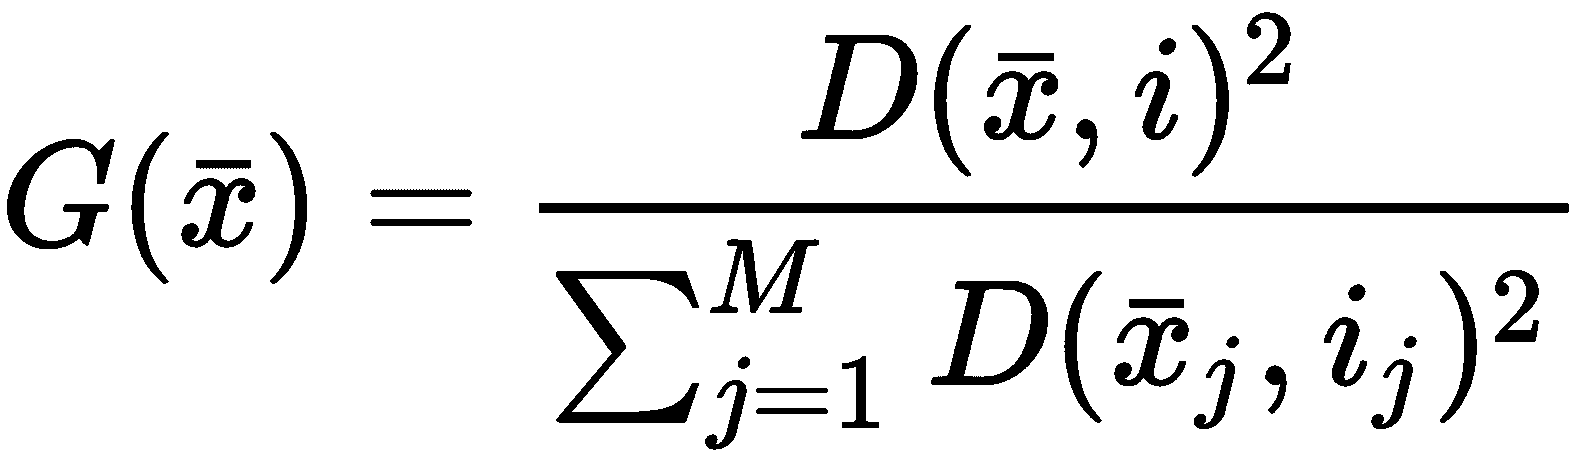

下载后(如技术要求部分所述),CSV 文件必须放在我们通常表示为<data_folder>的文件夹中。 第一步是加载数据集,并通过 Pandas DataFrame暴露的函数describe()进行全局统计分析,如下所示:

print(df.describe())

我强烈建议使用 Jupyter 笔记本(在这种情况下,命令必须仅是df.describe()),所有命令都将产生内联输出。 出于实际原因,在以下屏幕截图中,显示了表格输出的第一部分(包含八个属性):

数据集前八个属性的统计报告

当然,即使我们仅将注意力集中在子集上,我也请读者检查所有属性的值。 特别是,我们需要观察前八个属性之间存在的不同尺度。 标准差的范围是 0.01 到 350,这意味着仅由于一个或两个属性,许多向量可能极其相似。 另一方面,使用方差缩放对值进行归一化将赋予所有属性相同的责任(例如143.5和2501之间的界限为area_mean,而0.05和smoothness_mean之间的界限为smoothness_mean。 强迫它们具有相同的方差会影响因素的生物学影响,并且由于我们没有任何具体的指示,因此我们没有授权做出这样的选择)。 显然,某些属性在聚类过程中将具有更高的权重,我们将它们的主要影响视为与上下文相关的条件。